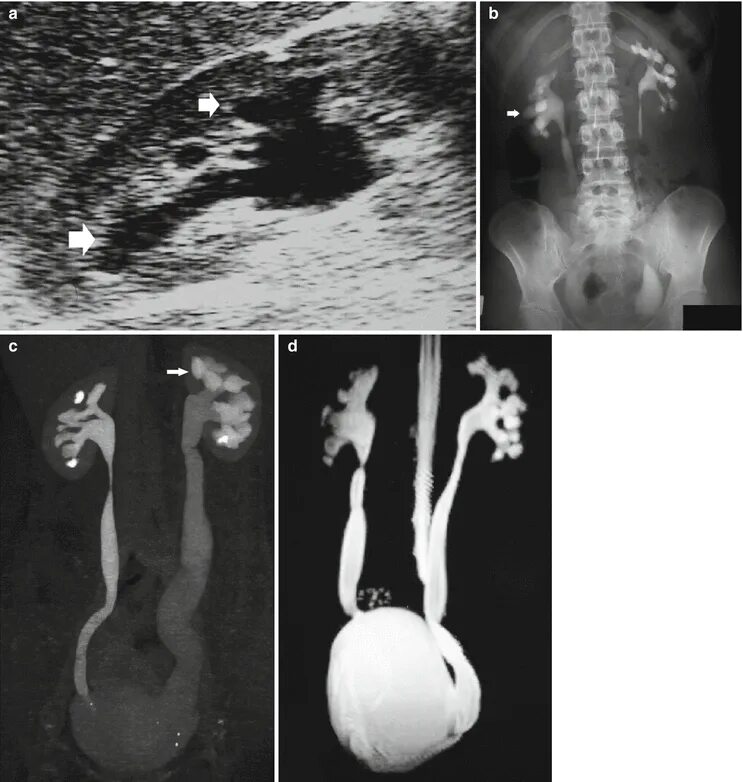

Мегауретер у детей что это